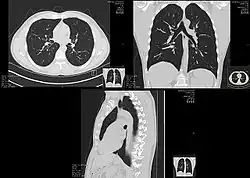

Lungs

A CT scan can be used for detecting both acute and chronic changes in the lung parenchyma, the tissue of the lungs.[41] It is particularly helpful because normal two-dimensional X-rays do not show such defects. A variety of techniques are used, depending on the suspected abnormality. For evaluation of chronic interstitial processes such as emphysema, and fibrosis,[42] thin sections with high spatial frequency reconstructions are used; often scans are performed both on inspiration and expiration. This special technique is called high resolution CT that produces a sampling of the lung, and not continuous images.[43]

Bronchial wall thickening can be seen on lung CTs and generally (but not always) implies inflammation of the bronchi.[44]

An incidentally found nodule in the absence of symptoms (sometimes referred to as an incidentaloma) may raise concerns that it might represent a tumor, either benign or malignant.[45] Perhaps persuaded by fear, patients and doctors sometimes agree to an intensive schedule of CT scans, sometimes up to every three months and beyond the recommended guidelines, in an attempt to do surveillance on the nodules.[46] However, established guidelines advise that patients without a prior history of cancer and whose solid nodules have not grown over a two-year period are unlikely to have any malignant cancer.[46] For this reason, and because no research provides supporting evidence that intensive surveillance gives better outcomes, and because of risks associated with having CT scans, patients should not receive CT screening in excess of those recommended by established guidelines.[46]